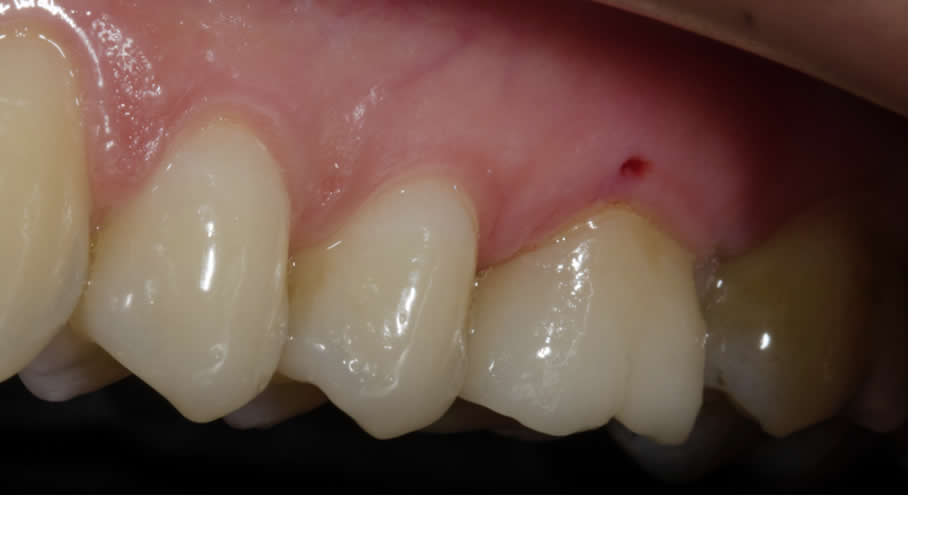

Elle permet d’envoyer énormément d’informations au prothésiste sur les états de surface, sur la répartition des masses, sur les caractérisations, sur les effets de translucidité.

Les recommandations actuelles sont d’utiliser une barrette de référence du teintier au minimum pour donner au prothésiste un élément de comparaison.

A cela peut être ajouté un travail sur la lumière avec les flashs. L’idéal étant de les déporter pour améliorer la perception des états de surface. Un éclairage avec un angle de 45° apporte une lumière douce qui met en valeur les lignes de transition.

Il faudra faire attention au changement de teinte lié à la déshydratation : une dent déshydratée paraîtra plus claire. Il est donc conseillé de prendre la teinte en début de séance et d’attendre la réhydratation de la dent avant de valider le résultat esthétique final.